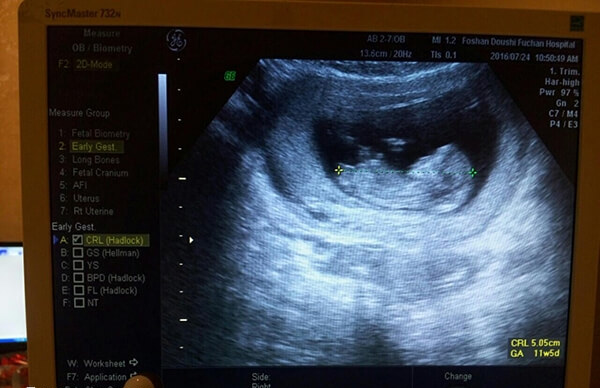

- 核实孕周、判断胚胎发育情况。根据孕囊的平均直径、胎芽大小、胎儿的头臀长判断孕龄,有助于中晚孕期间判断胎儿发育的状况。经阴道B超胎芽大于5mm时,应该见到胎心搏动。如果没有见到胎心搏动,提示有胚胎停止发育 的可能,应定期复查;